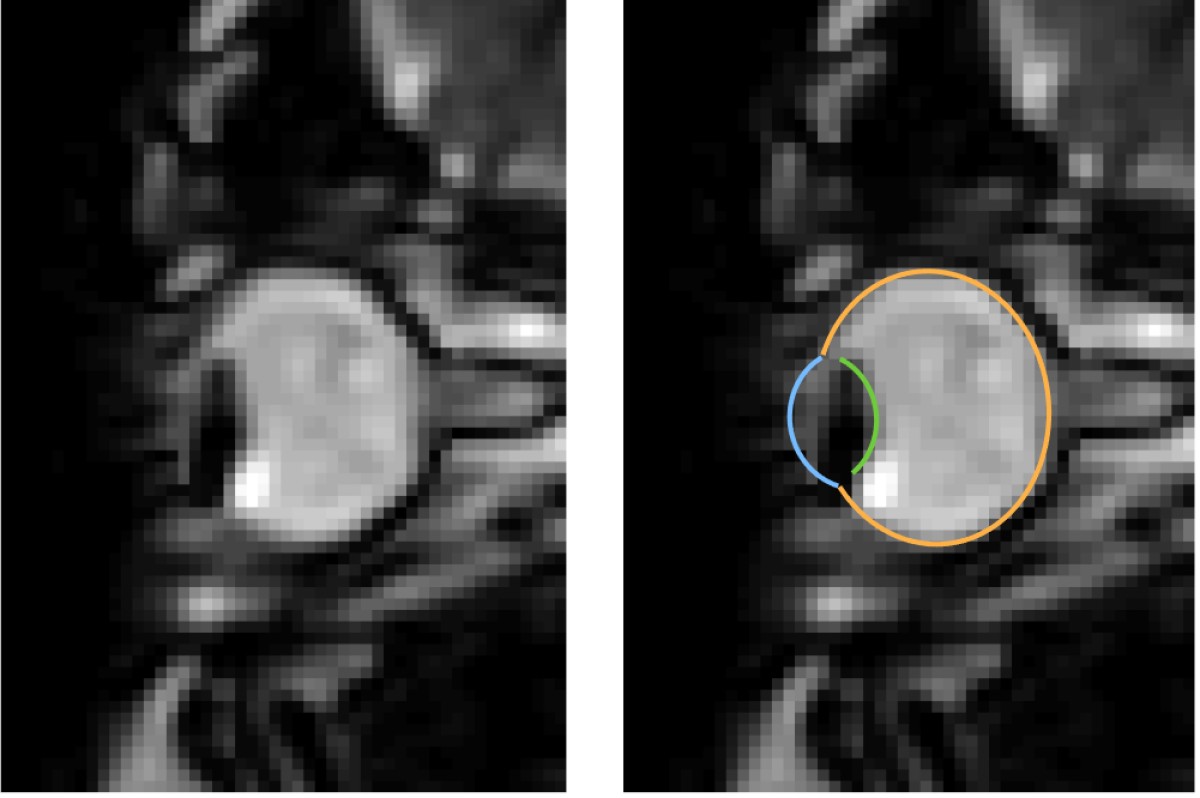

MRI images of eye movements during blinking: The eye is pulled back into the eye socket. The left image shows only the dynamic MRI data, the right image additionally shows the segmentation of the eye by the MREyeTrack. The photo corner consisting of six images shows the eye movement.© WWU - Johannes Kirchner

Eye movements are typically measured using eye-trackers, which are high speed cameras that film pupil position.” We were able to develop a method that captures eye movements in unprecedented temporal resolution using real-time MRI. Using this new method, we could show that the whole eyeball is being pulled back into the eye socket during a blink“, explains author Johannes Kirchner, research assistant at the Institute of Psychology at Münster University. The scientists from the University of Münster developed the method with co-author Prof. Tamara Watson from Western Sydney University.

MRI is a relatively slow procedure, the temporal resolution usually ranges between seconds or minutes. Eye movements on the other hand are fast and typically last only a few dozen milliseconds. Recent technological advances allowed the recording of 2-D MR images at a resolution of up to 20 milliseconds. Those ultrafast MR sequences were initially developed for cardiac imaging and haven’t been applied to the recording of eye movements. “We could reach a temporal resolution of 35 milliseconds. Total scan duration of only a few minutes already leads to the acquisition of over 10000 images. For actual eye-tracking, a fully automatic segmentation algorithm to analyse these images was needed”, explains co-author Prof. Markus Lappe, professor for cognitive neuroscience at the Institute of Psychology at the University of Münster. “With ‘MREyeTrack’ we have developed such a segmentation algorithm, which allows the fully-automated analysis of eye position and orientation in every single image.”